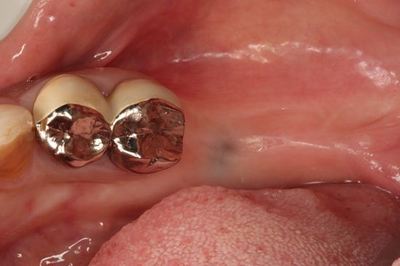

![]()

おくちでの適合を確認します。

このスリーブにドリルを挿入してドリリングします。